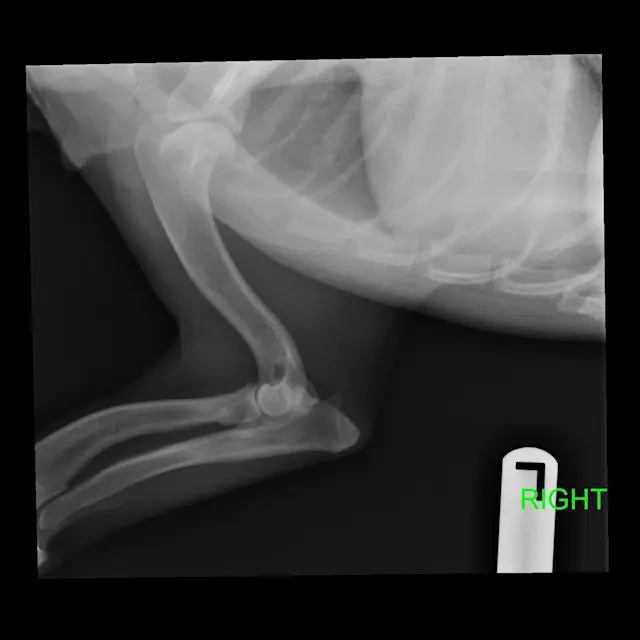

FIGURE 1

Radiographs of Ernest at 8 years of age at a recheck examination

On physical examination, Ernest had bilateral carpal valgus, with pain on manipulation of the carpus and mild hypertrophy of the shoulder musculature. On gait evaluation, slight scuffing of the left front paw was noted. Ernest also had bilateral pain/resistance on extension of the coxofemoral joints and mild atrophy of the quadriceps/hamstrings bilaterally; he also appeared to be “bunny hopping” in the hindlimbs when jogging or climbing stairs. Ernest’s BCS was 4/9, and the remainder of the examination, including a neurologic examination, was within normal limits. Ernest was diagnosed with OA and pain secondary to hip dysplasia and angular limb deformity.